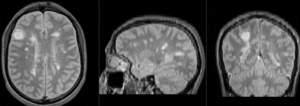

| + | |[[Image:RegLib_C04_registered1.gif|300px]]||baseline PD & contrast T1Gd after registration (click to enlarge) | ||

| + | |[[Image:RegLib_C04_registered2.gif|300px]]||baseline and follow-up PD after registration (click to enlarge) | ||

| + | |[[Image:RegLib_C04_registered3.gif|300px]]||baseline and follow-up T1Gd contrast after registration(click to enlarge) | ||